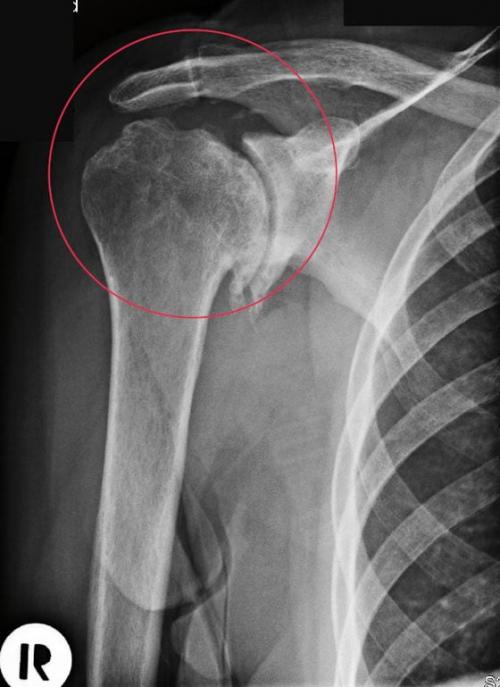

Хрустит плечо при вращении, что делать. Остеоартроз

Плечевой сустав щёлкает при остеоартрозе — дегенеративно-дистрофической патологии. Её развитие провоцируют эндокринные и метаболические нарушения, предшествующие травмы, интенсивные физические нагрузки и низкая двигательная активность. В сочленении начинают разрушаться хрящи, выстилающие поверхности костных головок. Это приводит к разрастанию краёв костных пластинок и формированию остеофитов (наростов) . Они давят на нервные окончания, расположенные поблизости мягкие ткани. Постепенно гиалиновые хрящи истончаются, утрачивают свои амортизационные свойства. Суставная щель частично ил полностью сращивается, плечо обездвиживается. Клиническая картина остеоартроза состоит из таких характерных признаков:

- боли, усиливающиеся при вращении плеча и практически исчезающие на конечной стадии патологии;

- утренняя припухлость сустава и скованность движений ;

- щелчки, возникающие при смещении костных головок на фоне истончения хрящевых тканей.

Обратите внимание на неровные края головки плечевой кости.

Если звуки появляются нечасто и пока не сопровождаются болью, то вполне возможно повернуть патологический процесс вспять. В терапевтические схемы врачи включают НПВС (Нурофен, Фастум, Вольтарен ) в виде мазей, гелей. Обязательно назначается курсовой прием хондропротекторов (Терафлекс, Структум, Артра) в течение нескольких месяцев, физиопроцедуры ( лазеротерапия , бальнеолечение, УВЧ-терапия), регулярные ежедневные занятия лечебной физкультурой.